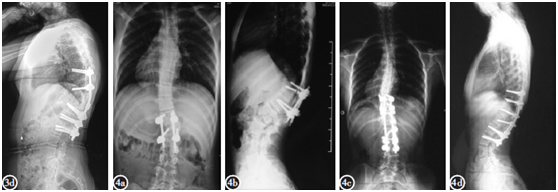

脊柱后凸手术

脊柱后凸手术,脊柱后突手术

如何矫正脊柱侧凸及后凸畸形

单一半椎体型先天性脊柱侧后凸初次手术失败的原因分析及翻修方法选择

严重脊柱后凸获矫正--多节段smith-petersen截骨技术

pso结合ponte截骨治疗脊柱后凸畸形